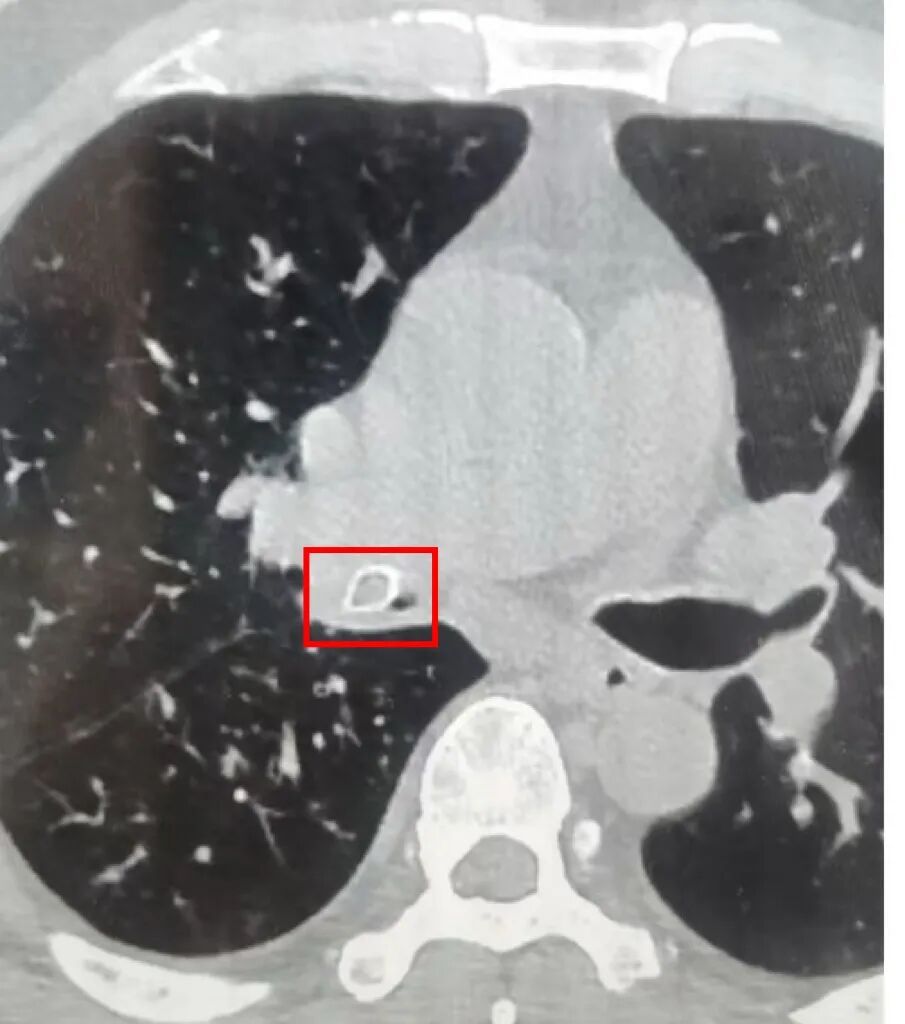

近日,50岁的张先生(化名)因反复发热、剧烈咳嗽前往同济大学附属上海市第四人民医院就医,结果发现右下肺已大面积感染,接近“烂肺”边缘。而罪魁祸首,竟是一枚“消失”的话梅核!

红框标出处为话梅核所在

“张先生的‘烂肺’其实是肺脓肿,是因话梅核完全堵塞右下支气管造成的。”上海四院呼吸与危重症医学科主任李兵介绍,人在吞咽或睡眠时,喉咙的会厌软骨本应关闭气管通道,但若此时突然吸气(如惊醒、呛咳),气管会瞬间开放,异物便可能“溜进”支气管。“话梅核完全堵塞右下支气管后,空气无法进入该区域,加上分泌物滞留无法排出,滋生大量细菌,导致阻塞性肺炎。如果不及时将异物取出,感染会蔓延至整个肺叶,甚至引发脓胸、败血症。”